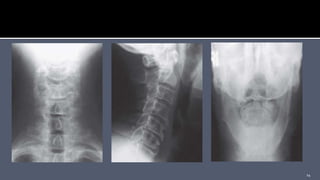

 Radiographs should include anteroposterior (AP), lateral, and

open mouth.

 Combined lateral mass displacement in excess of 7 mm or an

atlantodens interval (ADI) greater than 3 mm suggests

transverse ligament disruption.

 Radiographs shouldinclude anteroposterior (AP), lateral, and open mouth.  Combined lateral mass displacement in excess of 7 mm or an atlantodens interval (ADI) greater than 3 mm suggests transverse ligament disruption. 13